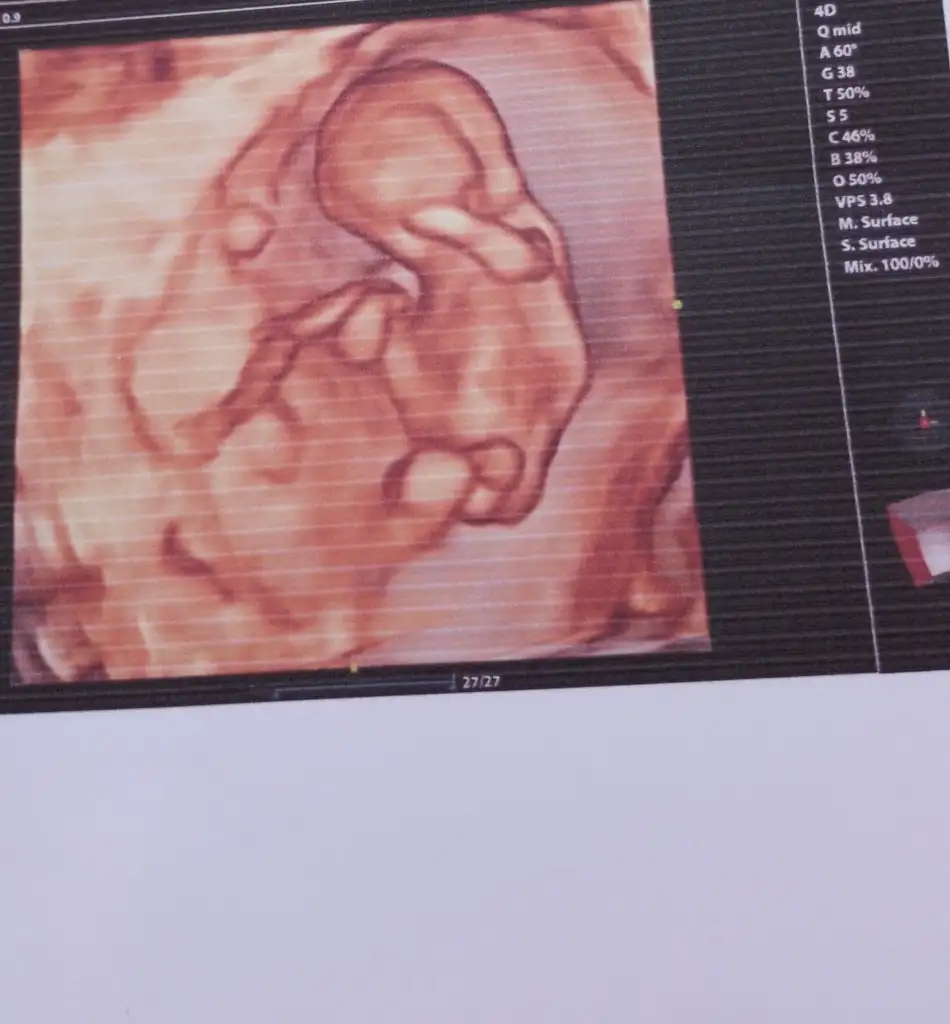

Benimkine de bakabilir misiniz doktorum 11+5te kız dedi 13+6da erkek dedi

İlk 3 fotoğraf 13+6

• IMG_4414.webp

IMG_4414.webp

28,8 KB · Görüntüleme: 108